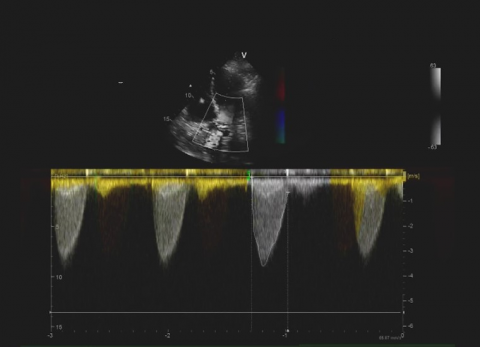

Prawe jamy serca i krążenie płucne

Przypadki dla początkujacych